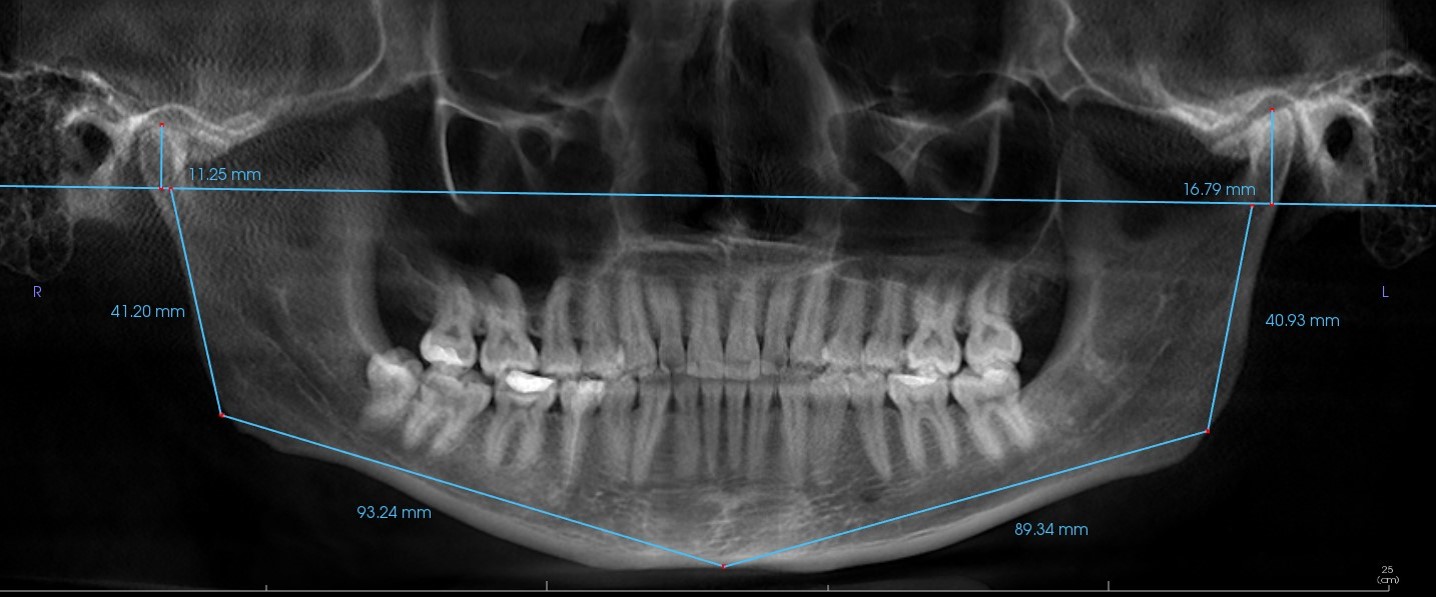

При обращении к стоматологу, будет проведено тщательное обследование полости рта и самого выбитого зуба. Врач оценит состояние зуба, определит наличие переломов корня или повреждений периодонтальных связок. Также будет проведена оценка альвеолы (лунки), из которой был выбит зуб.